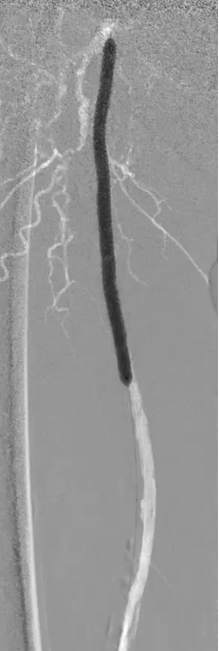

步进造影:股浅动脉起始重度狭窄、中段重度狭窄,腘动脉远端重度狭窄、胫前动脉、胫后动脉闭塞

V-18导丝配合多功能导管通过股浅动脉、腘动狭窄闭塞段,交换0.14导丝远端置于腓动脉中段

经导丝送入IVUS导管,股浅动脉近段重度狭窄、钙化明显,狭窄率大于90%

股浅动脉中远段及腘动脉重度狭窄、环周钙化明显

因患者股浅动脉及腘动脉狭窄闭塞段均严重钙化,选择使用振波球囊(6mm*80mm、5mm*80mm)

分别对股浅动脉、腘动脉狭窄闭塞段扩张(球囊至4atm,3级振波强度3个循环,5级振波强度3个循环);球囊切迹逐渐消失

IVUS提示病变段仍有局部重度狭窄,遂选择最新上市的”始祖鸟”紫杉醇药物涂层球囊(5*150mm、6*150mm )对残余狭窄进行扩张

IVUS提示病变段仍有局部重度狭窄,遂选择最新上市的”始祖鸟”紫杉醇药物涂层球囊(6*150mm、 5*150mm ) 分别对股浅动脉、腘动脉、胫腓干动脉逐段扩张,压力至工作压维持3分钟。

步进造影配合血管腔内超声诊断导管提示:股浅动脉全程、腘动脉、胫腓干动脉血流通畅,未见明显夹层、造影剂外溢,远端未见栓塞,膝下动脉如前。